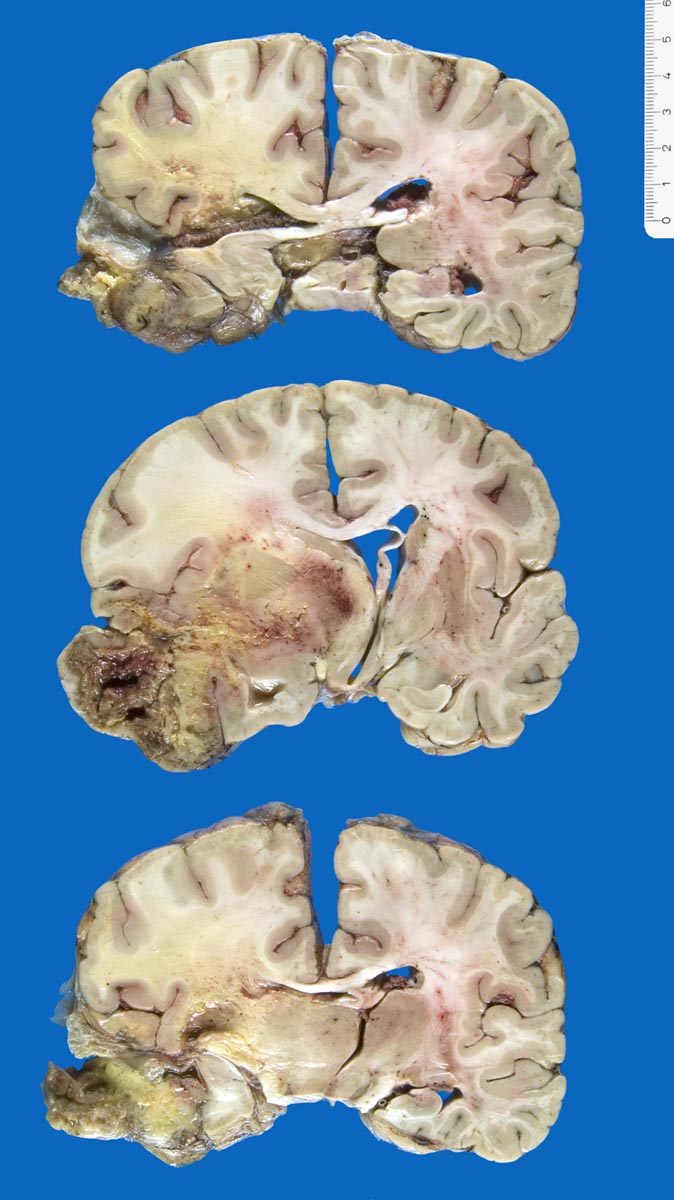

Morphologie:

Die Schnittfläche ist auffallend bunt. Dies ist bedingt durch ein Nebeneinander von graurotem vitalem Tumorgewebe, gelben Nekrosen, roten Einblutungen und gelegentlich grünlichen Gallertzysten.

• Zellreicher Tumor mit sehr unscharfer Begrenzung zum normalen Hirnparenchym (rechts unten).

Makroskopie

Pathologischer Befund